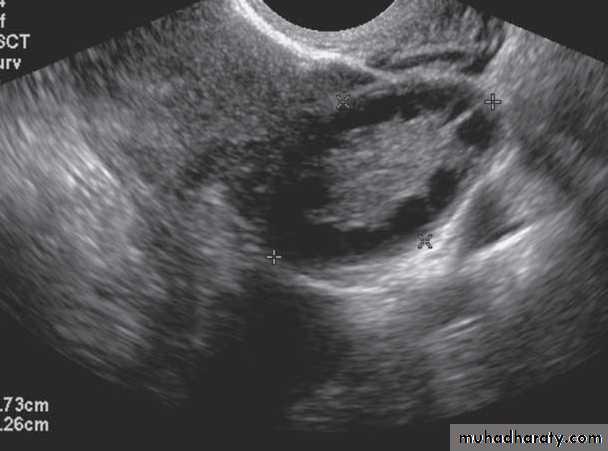

PCO by ultrasound criteria is defined as(1) Twelve or more antral follicles between 2 and 9 mm in size , classically referred to as the “string of pearls sign” when follicles located peripherally in the ovary.

(2) Increased ovarian volume ( 10 mL) in one or both ovaries.

Transvaginal ultrasound is more sensitive than a transabdominal one particularly in obese patients, but may not be appropriate to perform in a unmarried female.